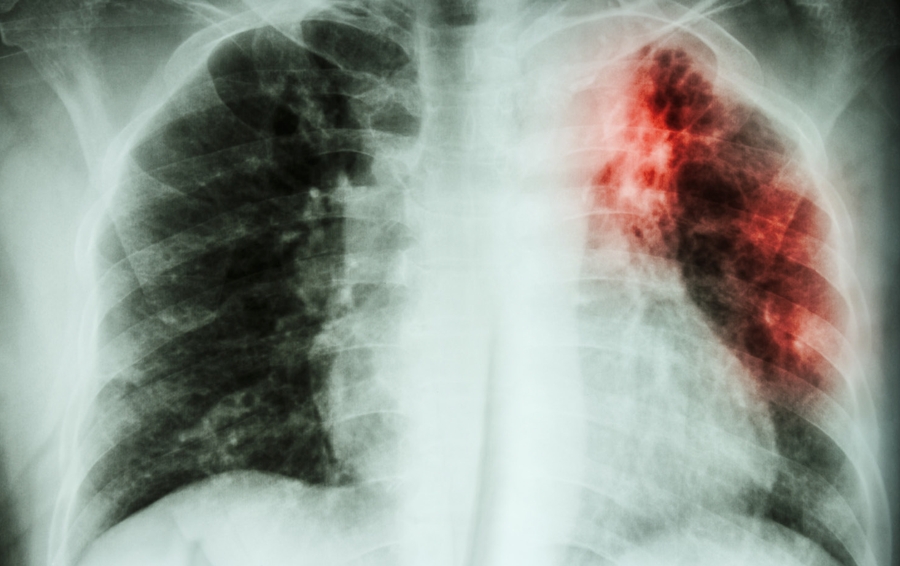

La tuberculosis, una enfermedad infecciosa provocada por el bacilo tuberculoso, persiste como una preocupación global para la salud pública. Este bacilo, una bacteria especialmente propensa a afectar los pulmones, se propaga a través del aire cuando una persona infectada tose, estornuda o escupe.

A pesar de su naturaleza contagiosa, la tuberculosis es una enfermedad que se puede prevenir y curar. A nivel mundial, aproximadamente una cuarta parte de la población ha sido infectada por el bacilo de la tuberculosis. Sin embargo, solo entre el 5 % y el 10 % de estas personas desarrolla síntomas y se enferma de tuberculosis.

Es crucial destacar que las personas que han sido infectadas, pero aún no han enfermado no son capaces de transmitirla a otros. La tuberculosis, una vez detectada, suele tratarse con antibióticos, y el tratamiento oportuno puede ser la clave para la recuperación. Sin embargo, si no se aborda de manera adecuada, la tuberculosis puede ser una enfermedad mortal.